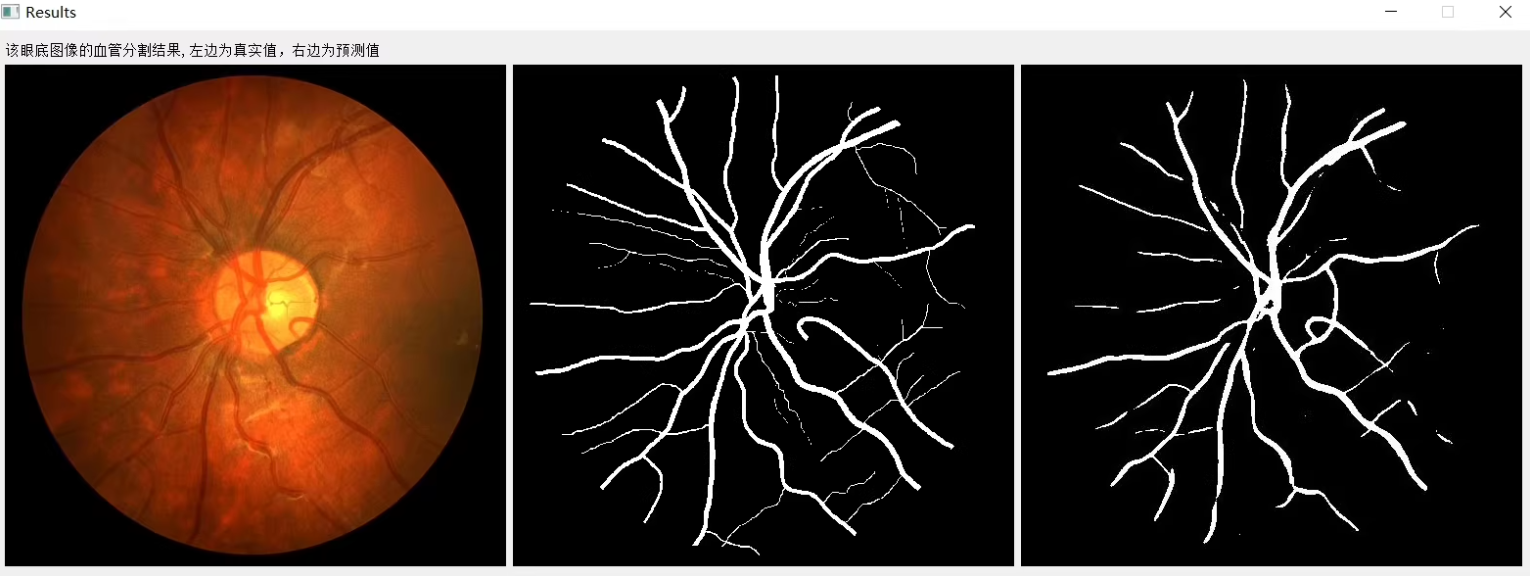

4. 结果评估与可视化

在完成模型训练后,可以使用训练好的模型进行眼底血管图像分割,并将结果可视化。